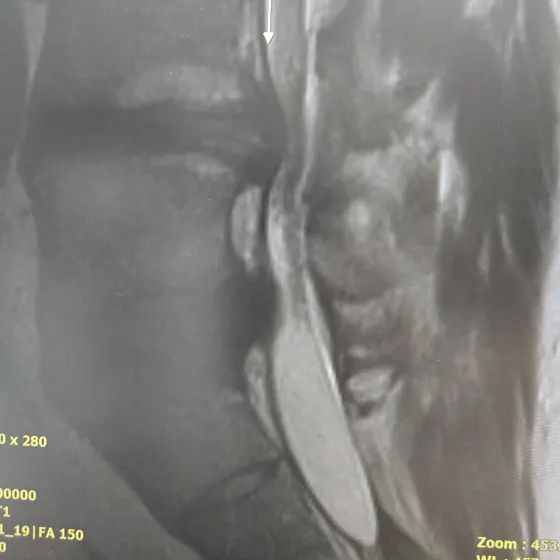

집사 허리디스크 소식입니다.

오늘 MRI를 찍고 왔는데

2년전 검사했을때보다 더 심각한

상황이라고 디스크제거술 권유 받았습니다. 다리저림과 통증이

심했을텐데 어떻게 버텼냐면서

선생님이 고개를 갸우뚱 하시더라구요

저도 이 아픔에 익숙하지 않고 늘 힘들 었는데 아픈거에 비해

생각보다 무던하게 버텨온것 같네요 스스로 몸을 망치고 관리 못해준 제 자신에게 너무 미안해서 눈물이 나더라구요..

"아 나 생각보다 훨씬 심했구나"

라는걸 오늘 다시 깨달았습니다.

현재 제가 할 수 있는건 신경성형술과

디스크제거술인데

신경성형술 :

400만원 / 부작용이 없음 / 일상생활 가능 / 재발가능성 있음 / 사람에따라 효과가 미비할 수 있음

디스크제거술 :

600만원 / 수술후 2주간 활동못함 / 한달간복대착용 / 전신마취해야함

/ 부작용 있을 수 있음

선택을 해야하는 상황에서

금전적인 문제도 그렇고 디스크제거술은 제 현재 상태에서 전신마취가 위험해서 안될 가능성도 있다네요.또한 고양이들을 돌봐줄 사람도 없거니와 부작용도 걱정되서요 그래서 내일 다른 병원 한곳 더 가보고 신경성형술쪽을 택할 것 같습니다. MRI비용 교통비 입원비등 추가적인 비용이 드는데 있어서 시술을 못할뻔 했지만 "이나바흐"님께서 추가로 또 도움 주셔서 할 수 있게 되었습니다. 정말 진심으로 감사드리고 고마워요